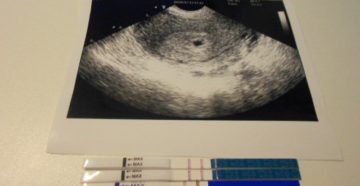

Нежелательная беременность на ранних сроках, что делать — узнай подробно! У любой женщины, начавшей жить…